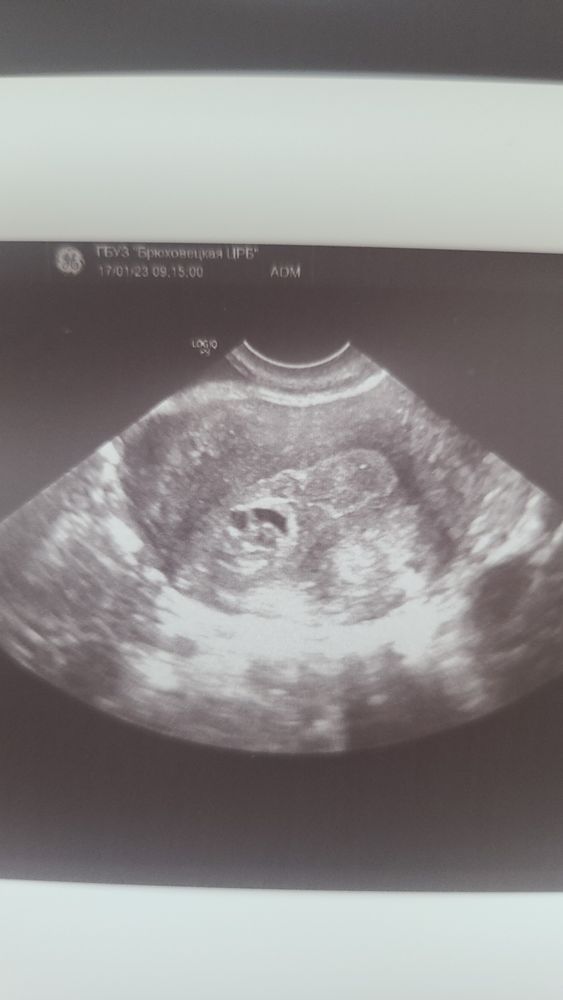

Helga, Изображение

Екатерина , это что я нашла в интернете и что говорят врачи 🤦‍♀️ Но у вас ведь было эко ? Как тогда это возможно 🤷‍♀️